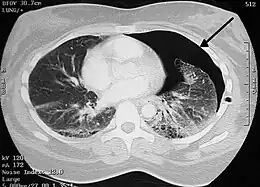

Image from a computed tomography (CT) scan of the chest. On the right (left side of the patient) there is a black area suggesting free air inside the chest

CT scan of the chest showing a pneumothorax on the person's left side (right side on the image). A chest tube is in place (small black mark on the right side of the image), the air-filled pleural cavity (black) and ribs (white) can be seen. The heart can be seen in the center.

The thoracic cavity is the space inside the chest that contains the lungs, heart, and numerous major blood vessels. On each side of the cavity, a pleural membrane covers the surface of lung (visceral pleura) and also lines the inside of the chest wall (parietal pleura). Normally, the two layers are separated by a small amount of lubricating serous fluid. The lungs are fully inflated within the cavity because the pressure inside the airways (intrapulmonary pressure) is higher than the pressure inside the pleural space (intrapleural pressure). Despite the low pressure in the pleural space, air does not enter it because there are no natural connections to air-containing passages, and the pressure of gases in the bloodstream is too low for them to be forced into the pleural space.[13] Therefore, a pneumothorax can only develop if air is allowed to enter, through damage to the chest wall or to the lung itself, or occasionally because microorganisms in the pleural space produce gas.[13] Once air enters the pleural cavity, the intrapleural pressure increases, resulting in the difference between the intrapulmonary pressure and the intrapleural pressure (defined as the transpulmonary pressure) to equal zero, which cause the lungs to deflate in contrast to a normal transpulmonary pressure of ~4 mm Hg.[28]